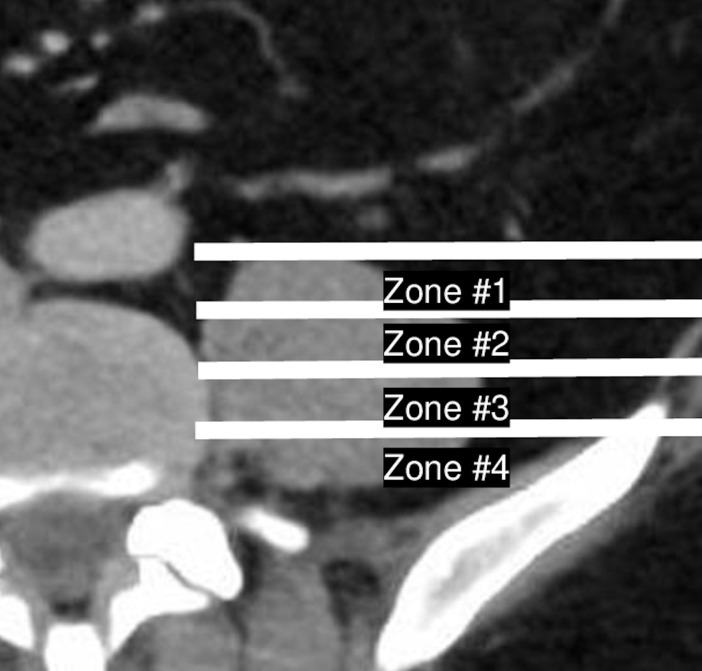

Following IRB approval (#5220184), we performed a radiographic analysis of 100 patients who received abdominal CT imaging (GE Discovery 750 HD 64 slice CT Scanner) between December 2021 and April 2022. Patient consent was not required due to the nature of this retrospective radiographic study. All patients demonstrated clear axial and sagittal CT images and were aged between 18 and 80 years. Patients with history of spinal surgery, infection, or malignancy were excluded from review. Radiographic, demographic, and anthropometric data were retrieved using IMPAX6 (Agfa-Gavaert, Mortsel, Belgium) picture archiving and communication system. Radiographic measurements were conducted by 3 independent reviewers (J.R., S.M., and G.H.). To perform each measurement, a midsagittal view was first used to identify the disc space center. An axial slice of the disc space was then viewed, with the axial cut extracted from the mid cut of the disc space at each level. To ensure standardized measurements, this axial cut was utilized to measure both the ATP approach and TP approach as well as the percentage of obstruction caused by nonneurological structures within both approaches. The TP approach was characterized as the plane of the psoas muscle between the anterior and posterior margins divided into four equally sized zones based on the method described by Moro et al (Figure 1).5 Measured on the same slide, the ATP approach was defined bilaterally as the distance between the anteromedial aspect of the psoas major and the posterolateral aspect of the aorta, inferior vena cava, or common iliac vessels, depending on disc level and side ( Figure 2).1,6–8 The presence and degree of obstruction by each anatomical structure within the ATP and TP approaches were then calculated using the methods described in Figure 3. The percentage of time, or frequency, a given anatomical structure obstructed the surgical approach (ATP or TP) was calculated as the quotient of the number of times the structure was observed within the ATP or TP approach within the cohort, divided by 100 (the total number of patients included in this study).

Figure 1.

Transpsoas approach characterization by division of the psoas major into four zones. The psoas major was divided anterior-to-posterior into four equally sized zones using IMPAX6 measurement software.